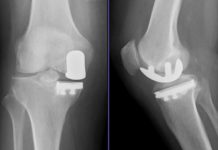

Knieprothese: Risiken und Chancen einer Operation

Welche Operationsmethoden gibt es für eine Knieprothese? Welche Prothesentypen sind zu empfehlen und wie groß sind die Heilungschancen? Hier erhalten Sie Informationen rund um die Implantation einer Knieprothese.

Diese Knieprothesen werden häufig verwendet

Wenn die Arthrose fortgeschritten ist, raten Ärzte zu einer Knieprothese. Wie ist eine Knieprothese aufgebaut und welche Arten gibt es? Hier werden diese Fragen beantwortet.

Künstliches Kniegelenk: Der OP-Tag

Nach dem Einsatz eines künstlichen Kniegelenks bleibt man etwa 7 bis 10 Tage im Krankenhaus. Was kommt vor und nach der OP auf Sie zu?

Wenn ein Roboter bei der Knie-OP assistiert

Am Sankt Marien-Hospital Buer werden jetzt Knieprothesen mit Hilfe eines Roboters eingesetzt. Für Chirurgen ist das System eine Arbeitserleichterung, vollumfänglich nachgewiesen ist die Evidenz aber noch nicht.